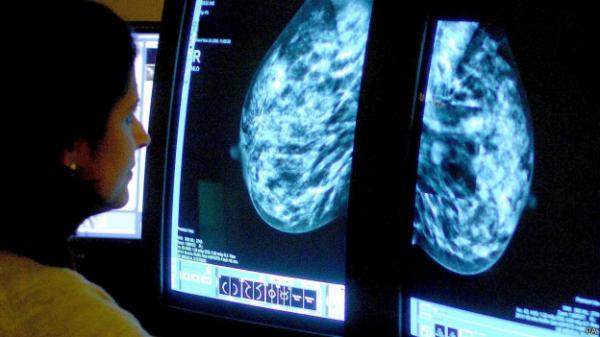

يقول علماء إن البحوث الخاصة بمرض سرطان الدم (اللوكيميا) قد تقود إلى اكتشاف عقاقير جديدة لعلاج أمراض سرطان الثدي المستعصية.

وقال فريق بحثي من جامعة غلاسغو في اسكتنلدا إن أحد أجزاء الحمض النووي الذي يسبب اللوكيميا له دور في توليد بعض الأورام الأخرى، الأمر الذي قد يساعد في البحث عن عقاقير جديدة.

ويقول باحثون آخرون إنهم اتخذوا خطوات أولية باتجاه إجراء فحوصات للدم من شأنها تحديد سرطان الثدي.